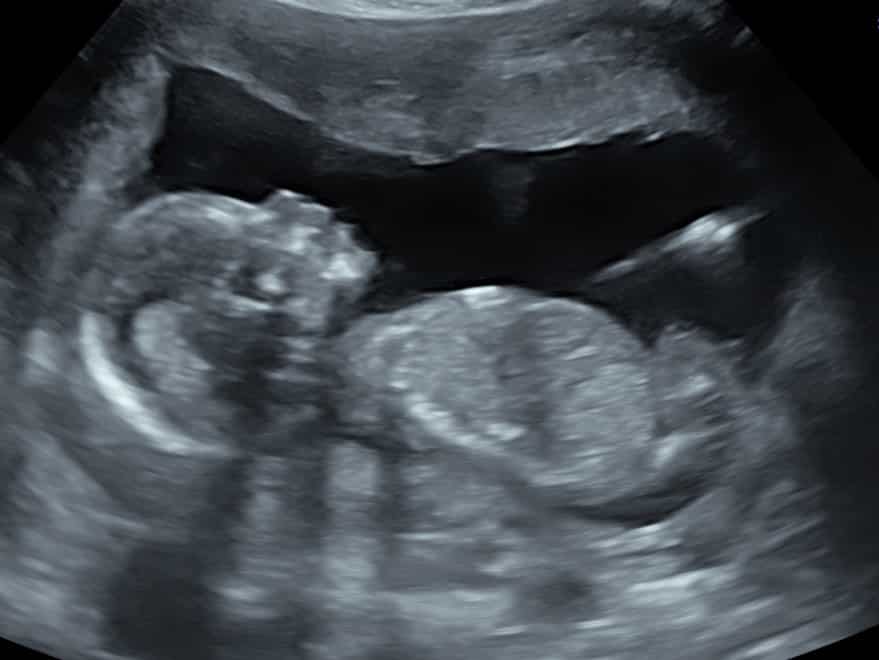

Our Specialist Sonographers start every scan with a fetal well-being check. They will confirm single or multiple pregnancy and check the baby/babies are growing normally. They will show baby’s position & placenta, confirm, visualise & listen to the heartbeat, observe the abdominal contents & brain, as well as detect some abnormalities.

This scan is all in 2D; the sonographer will move onto taking the measurements of baby and will provide the information to your personal scan assistant, to be added to your well-being report.

We will round off your scan by taking photos of each measurement and of baby.